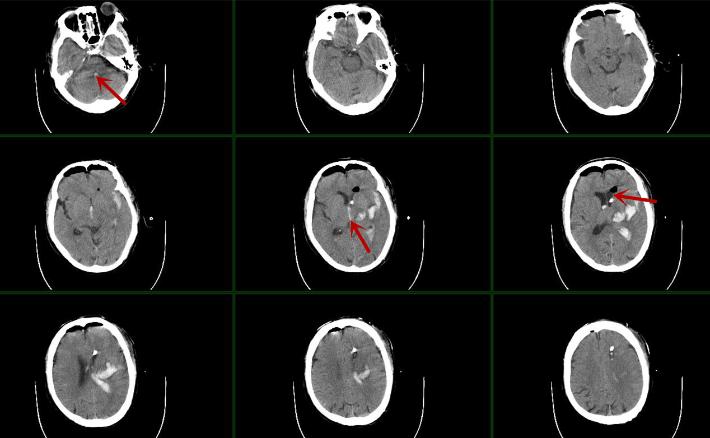

辅助检查:头颅CT(2020-11-10):左侧基底节区脑出血并破入丘脑及脑室系统。

术前考虑血肿破入脑室系统(左侧脑室铸型,三脑室及四脑室铸型),考虑梗阻性脑积水发生可能性大。脑内血肿量少,不考虑手术清除。

术后第一日,患者神志较前好转,GCS评分10分,神志昏睡。复查颅脑CT:左侧脑室血肿较前明显减少,三脑室、四脑室血肿密度减低。